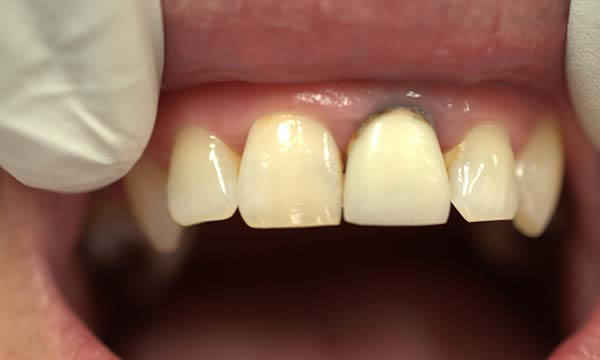

Case F

This gentleman came to see me after his crown decorated. He was fed up with being called a pirate by his grandchildren and decided to do something about the gap.

Due to an absence of infection and an atraumatic extraction, the removal of the tooth was followed by immediate implant placement. The implant was restored with an Atlantis abutment and bonded crown.

Before Treatment